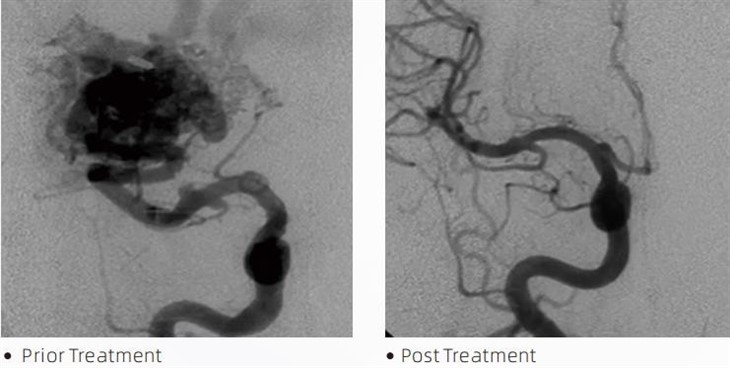

용암증권 시세 표시기색전 접착제는 뇌동맥류, 동정맥 기형 및 종양과 같은 상태를 치료하기 위해 최소 침습 절차 중에 중재적 신경방사선 전문의가 사용하는 의료 기기입니다. Lava 색전 접착제는 의료 전문가와 환자 모두에게 안전, 사용 용이성 및 효과 측면에서 다양한 이점을 제공합니다. Lava는 혈관을 빠르고 효율적으로 봉쇄할 수 있습니다. 이 과정에는 접착제를 표적 혈관에 직접 주입하는 과정이 포함되며, 여기서 접착제는 동맥류 또는 기형을 채우는 캐스트와 같은 덩어리로 중합되고 경화됩니다. 그런 다음 병변으로 가는 혈류를 효과적으로 차단하여 파열을 방지하고 영구적인 손상이나 뇌졸중의 위험을 줄입니다. 용암에는 용암-12, 용암-18 및 용암-34이 포함됩니다. 각 제형은 특정 임상 요구를 충족하도록 설계되었습니다. Lava-18는 일반적인 사용을 위한 표준 제형입니다. Lava-34는 고유동 용기용 고점도 접착제입니다. 반면 Lava-12는 점도가 낮고 유동성이 높아 말단 미세혈관을 허용합니다. 이러한 옵션을 통해 중재적 신경방사선 전문의는 최적의 결과를 보장하기 위해 적합한 Lava 제제를 선택할 수 있습니다. Lava의 가장 두드러진 특징 중 하나는 비점착성입니다. 이 물질은 목표 영역에 도달할 때까지 안정적으로 유지되도록 특별히 제조되었습니다. 이 특성은 Lava 색전 접착제가 동맥 내에 정확하게 위치할 수 있고 주변 조직에 달라붙거나 결합하지 않고 동맥에 남아 있을 수 있음을 의미합니다.